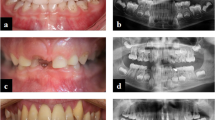

Hyp mice presented with decreased alveolar bone volume per total volume (AB BV/TV) when compared WT mice in both sexes (Fig. 1 and Supplemental Table 1). Scl-Ab increased AB BV/TV regardless of genotype or sex (Fig. 1). Overall, WT mice exhibited greater increases in AB BV/TV when compared to Hyp mice (males: 50% WT, 45% Hyp; females: 25% WT, 11% Hyp). Increased AB BV/TV following Scl-Ab treatment was primarily due to increased alveolar bone volume (Supplemental Table 1). Scl-Ab increased alveolar bone volume regardless of genotype or sex, although the post hoc comparisons were not significant in the Hyp female mice.

a Representative sagittal microCT images of hemimandibles (top). b Alveolar bone volume per total volume and (c) tissue mineral density in male (left) and female (right) mice. Data are presented as the mean ± standard deviation. Results from the two-way analysis of variance (ANOVA) are presented in the figure legends. Significant post hoc treatment differences between animals of the same genotype are presented as a horizontal bar. P value thresholds are indicated with stars above the bars: *P < 0.05; **P < 0.01; ***P < 0.001; ****P < 0.000 1. The sample sizes ranged between 10 and 14 samples per group

By contrast, increases in alveolar tissue mineral density (AB TMD) in response to Scl-Ab were only observed in male mice. There was also a significant genotype-by-treatment interaction in male mice, attributed to the significant increase in WTs but a lack of a post hoc difference in Hyp mice. No significant differences in alveolar tissue mineral density were observed in female mice.